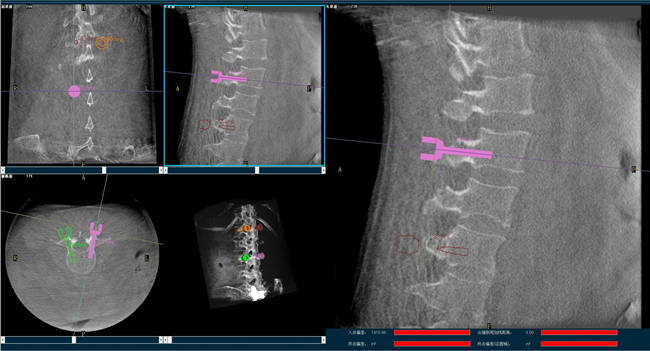

迄今,術(shù)前規(guī)劃已經(jīng)成為骨科手術(shù)的“前哨守衛(wèi)”,目前的脊柱外科手術(shù)機(jī)器人可以通過(guò)人工智能算法做到精準(zhǔn)的脊柱分節(jié)段識(shí)別并模擬重現(xiàn)患者的生理特征與骨骼排列,讓手術(shù)既準(zhǔn)確又安全;尤其在脊柱外科手術(shù)中可以發(fā)揮很大作用,避免產(chǎn)生對(duì)周?chē)窠?jīng)、椎管內(nèi)脊髓的損害,減少并發(fā)癥的出現(xiàn)。

以椎弓根螺釘置入手術(shù)為例,有時(shí)候?yàn)榱藴?zhǔn)確定位,甚至需要將椎弓根螺釘多次進(jìn)出、反復(fù)選擇,這樣無(wú)疑就增加了脊髓神經(jīng)損傷的風(fēng)險(xiǎn),降低了螺釘把持力。但脊柱外科手術(shù)機(jī)器人可以在術(shù)前規(guī)劃把手術(shù)入路、方向、釘子的深度都做好規(guī)劃,手術(shù)前就在電腦上規(guī)劃好進(jìn)釘?shù)奈恢?,在手術(shù)中利用機(jī)器人系統(tǒng)“(脊柱)分節(jié)段單椎體識(shí)別”、“釘棒一體化”、“術(shù)中全程可視”等特性,做到“一步到位”,因此,比起傳統(tǒng)手術(shù),機(jī)器人手術(shù)更加安全。同時(shí),目前機(jī)器人技術(shù)的透視檢查時(shí)長(zhǎng)、每顆螺釘置入時(shí)長(zhǎng)和住院時(shí)長(zhǎng)均比術(shù)中使用3D-CT導(dǎo)航更短,提升手術(shù)效率。